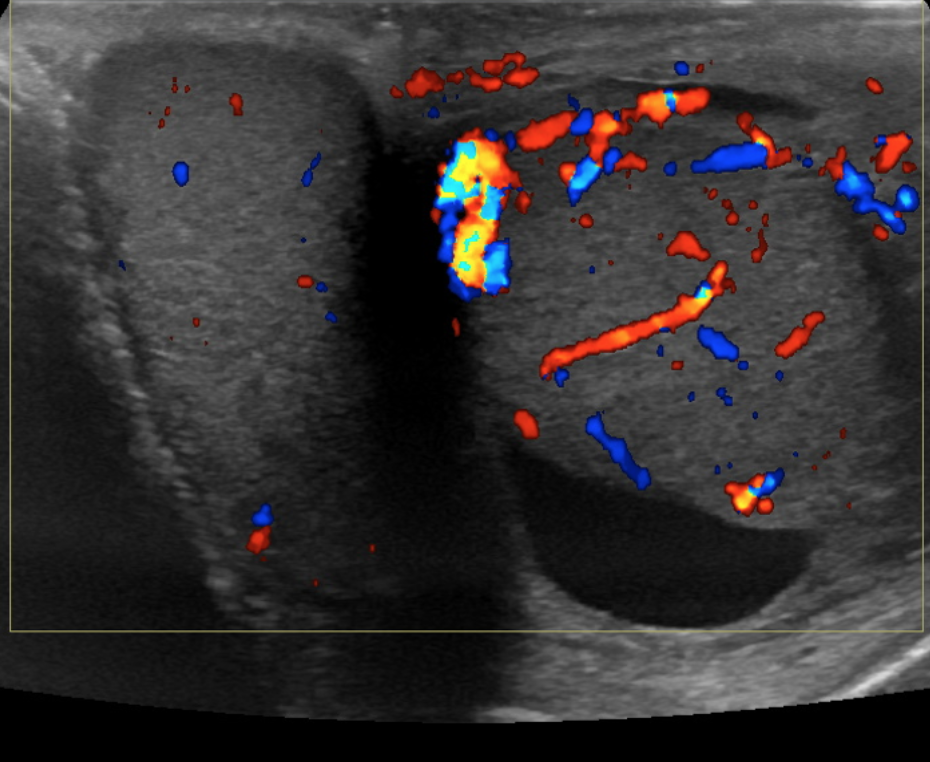

Epididymo-Orchitis

• Inflammation of the epididymis and testicle

• Presents as an enlarged and hyper-emic (increased blood flow) testicle/epididymis